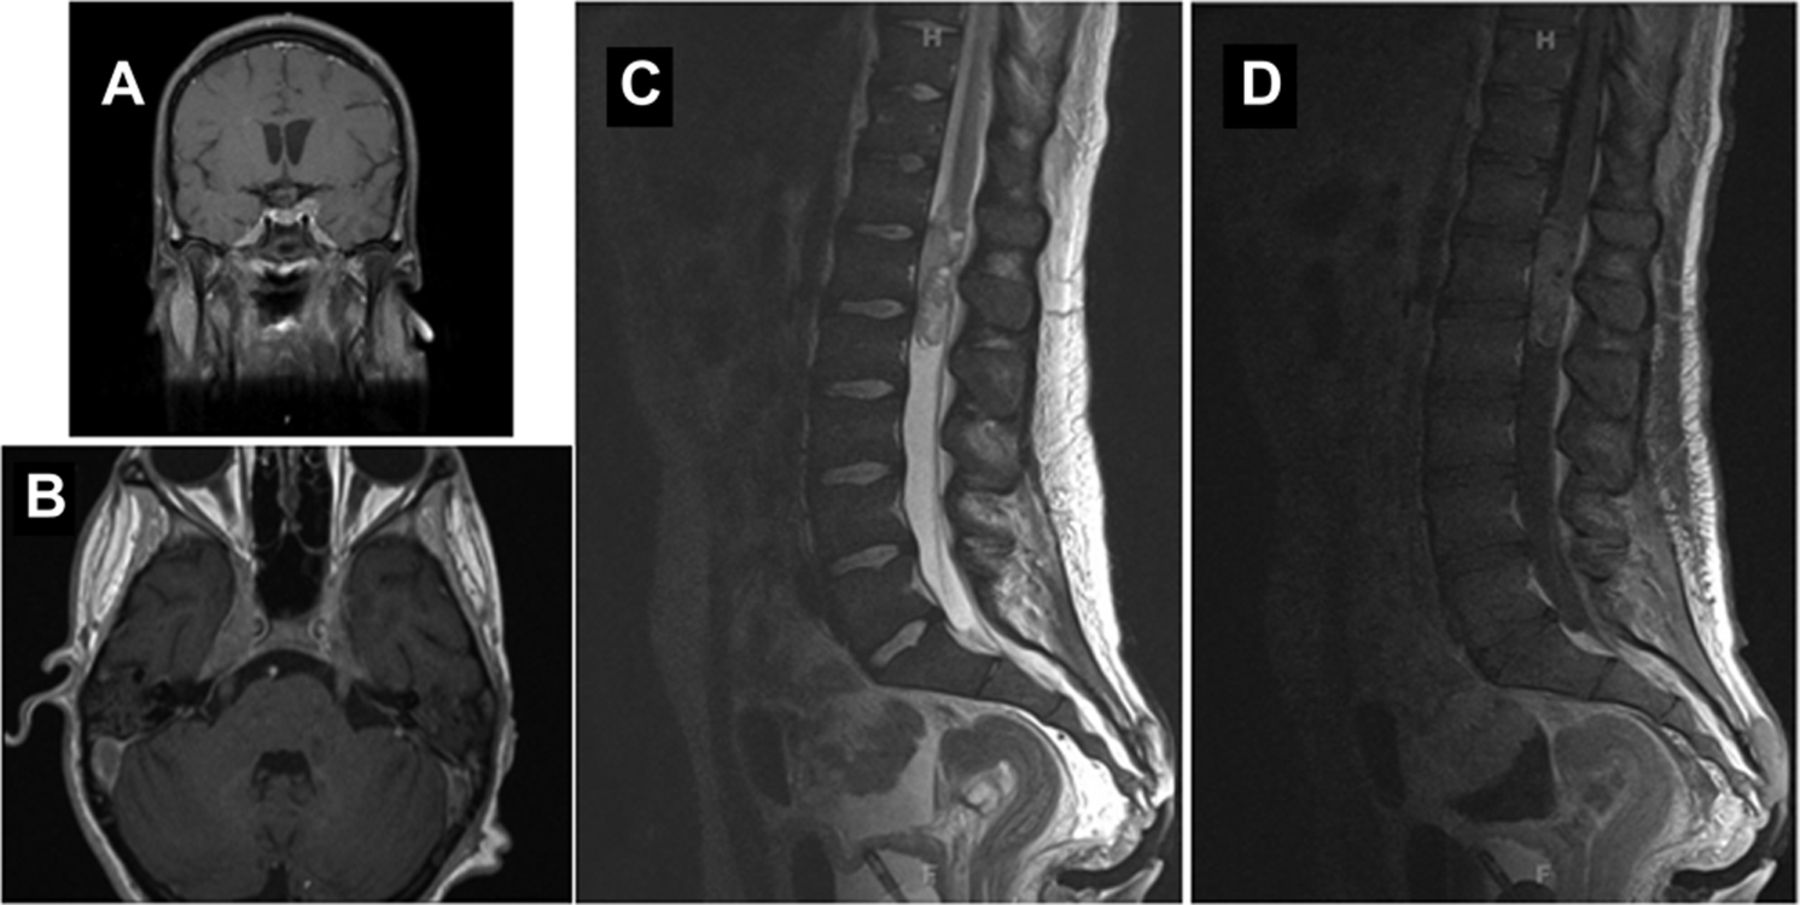

重复脑部MRI与钆(图1一个)和专用快速成像采用稳态收购系列(图1 b脑神经增强)展示了多个领域,包括双边眼球运动的,三叉神经,外展神经,面部,脊副神经神经以及增强群众松果体和软组织的双边三叉洞穴。脊柱MRI (图1中,C和D)与钆展示多个局部病变在脊髓中央管以及不同类地提高硬膜内的,类似胸腰椎质量。

重复与大脑演示了对称钆增强MRI (A)双边三叉神经在三叉洞穴。(B)快速成像采用稳态收购系列展示了增强双边海绵窦内,双边颈静脉孔,以及面部和蜗神经。胸腰椎脊柱(C)的MRI T2和T1 (D) postgadolinium序列证明不同类地提高硬膜内的,类似胸腰椎脊柱质量。